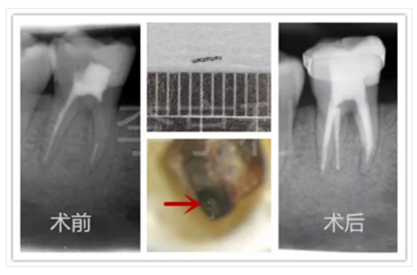

37術(shù)前診斷為無癥狀性根尖周炎,因轉(zhuǎn)診醫(yī)生在開髓時發(fā)現(xiàn)根管為C型,故轉(zhuǎn)至我處;在疏通根管時發(fā)現(xiàn)#10K銼分離,但未阻擋工作長度且顯微鏡下也無法暴露斷械,選擇進(jìn)行常規(guī)根管治療;1年后回訪發(fā)現(xiàn)根尖周暗影消失,37無任何臨床癥狀,根管治療判斷為成功